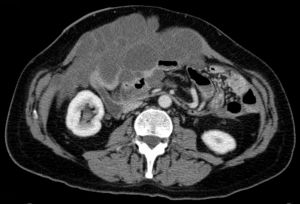

(4)CT檢查:肝脾受壓縮小,肝脾邊緣出現扇貝樣缺損腹膜增厚,腹腔內大量水樣低密度影,CT值20Hu,明顯高於腹水顯示腹腔和盆腔瀰漫性囊性腫塊囊腫大小不等,多在1cm以下,大網膜腹膜浸潤增厚;病灶CT值較低,多在3Hu左右;肝臟邊緣呈多發扇性凹陷,無肝實質轉移;大量腹水,常有分隔現象,腹水呈膠凍樣,密度較低,推壓腸管向中心移位